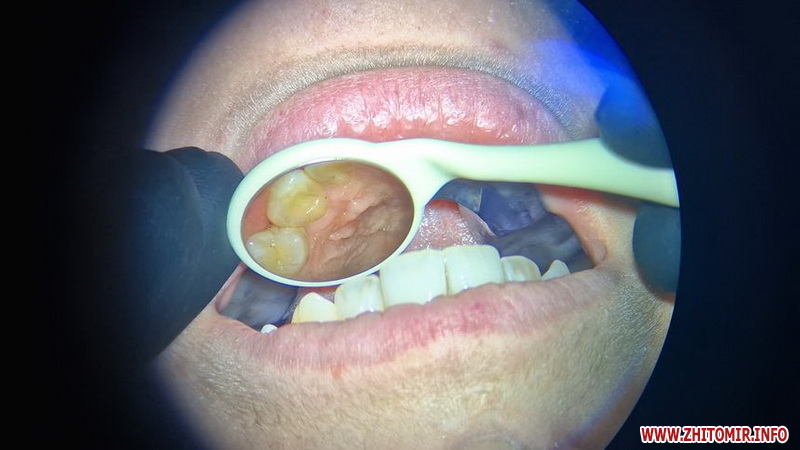

«У нас є три мікроскопи. Деякі хірургічні операції проводяться з мікроскопом, наприклад, обтікальна хірургія, ендодонтія. Також ортопедія, наприклад, вініри, де потрібна точність», - говорить головний лікар клініки «Vivita Dental» Артем Приборецький.